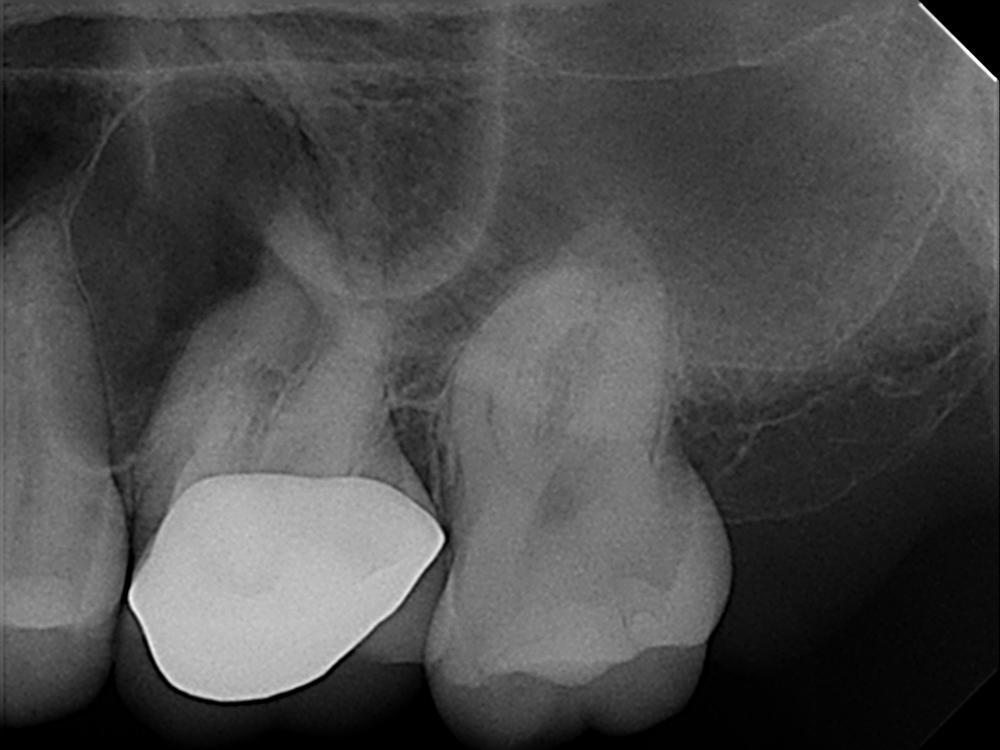

This case was referred to me by a doctor who was unable to negotiate his patient’s tortuous, ledged, and calcified canals, possibly because he did not have the ideal instruments for the case. During treatment, I negotiated the patient’s canals to apex using my #8 and #10 files. From there, I used EdgeGlidePath by EdgeEndo, which performs ideally in tight canals. When it began to bind after 1–2 mm, I paused to irrigate the area, recapitulated with my #10 file, and reentered with the EdgeGlidePath file to length.

Thanks to the flexibility and ease of use offered by EdgeOne Fire files, I completed this root canal rapidly and safely. Preop and postop images taken 4 months apart display signs of successful healing and an absence of a fistula. I think these files are great tools that every clinician should have.

Preop vs. Postop Radiographs taken 4 months apart